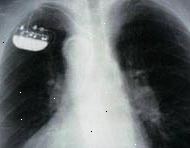

Εμφανίζεται εδώ είναι μια ακτινογραφία θώρακος. Το μεγάλο, λευκό χώρο στη μέση είναι η καρδιά. Οι σκοτεινές χώρους σε κάθε πλευρά είναι οι πνεύμονες. Το μικρό αντικείμενο στην επάνω αριστερή γωνία είναι ένα εμφυτευμένο βηματοδότη.